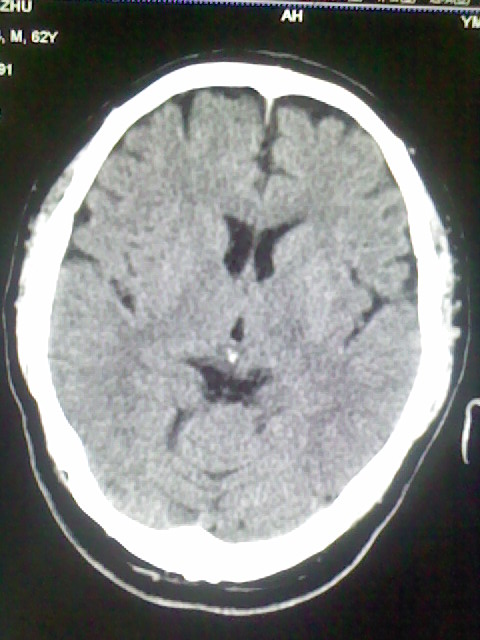

标题: CT15555:头痛 10余日 来诊大家帮忙看看 [打印本页]

标题: CT15555:头痛 10余日 来诊大家帮忙看看

脑萎缩

脑沟、裂增宽,提法脑萎缩,建议mt检查。

脑萎缩,以小脑为著。

脑沟、裂增宽,提示脑萎缩

老年脑

支持轻度脑萎缩。